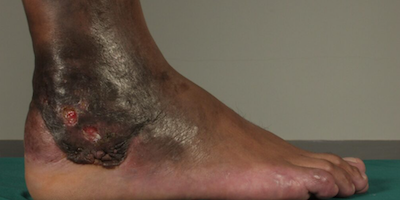

Các biểu hiện lâm sàng của Mycetoma do nấm và Actinomyces rất giống nhau. Thường gặp ở bàn chân, cẳng chân, bàn tay, cánh tay, có khi ở mông và lưng ngực,... Khoảng 70% trường hợp bệnh ở chân (chân trái nhiều hơn chân phải).

Tổn thương cơ bản là những đám hạt, cục to nhỏ không đều, không cùng tuổi, gồ ghề trên mặt da kèm theo sưng, phù nề vùng da tổn thương, sau đó dần dần xuất hiện các lỗ dò chảy dịch vàng lẫn mủ đục. Đôi khi có các hạt màu vàng, trắng, nâu, đen hay hơi đỏ phụ thuộc vào từng loại nấm gây bệnh. Khi không điều trị kịp thời bệnh sẽ lan xuống sâu, vào xương dẫn đến xốp xương.

Bệnh có thể kéo dài hàng chục năm làm cho bệnh nhân bị suy kiệt dẫn đến tử vong.

Tam chứng Mycetoma:

+ Vùng chi sưng, không đau

+ Nhiều lỗ dò chứa mủ để thoát các hạt

+ Vị trí thường gặp ở bàn chân.